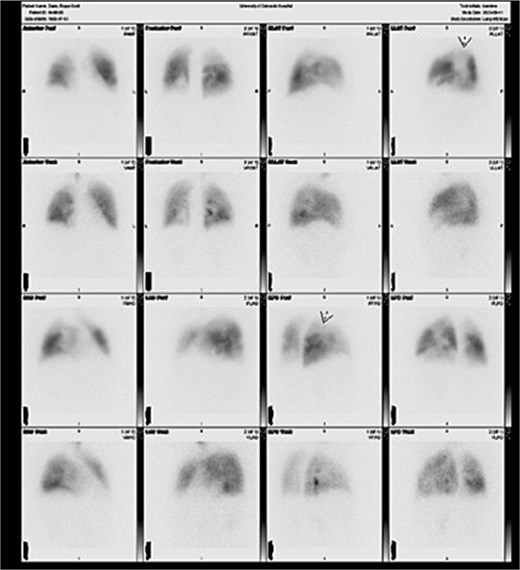

Under general anesthesia, a pulmonary artery catheter and transesophageal echocardiography confirmed preoperative findings. CABG was performed with left internal mammary artery to the left anterior descending artery and saphenous vein graft to the right coronary artery. Bilateral pulmonary endarterectomy with right pulmonary artery patch angioplasty was completed. Disease was Jameson class I on the right and class II on the left (Fig. 2). The patient then underwent aortic valve replacement with an Edwards Inspiris tissue valve, ascending aorta repair, PFO closure, and LAAL. No intraoperative complications occurred. He was extubated on postoperative day 1. Echocardiogram showed a mildly enlarged right ventricle with normal pressures. Mean PA pressures were 24, 18, 24, and 15 mmHg on postoperative days 1–4. He was discharged on day 8 requiring 3 L oxygen at rest and 8 L with exertion. At 6 months, he required no supplemental oxygen and reported improved exercise tolerance. Follow-up V/Q scan showed markedly improved bilateral perfusion (Fig. 3).

Six-month postoperative V/Q scan demonstrating interval improvement in bilateral pulmonary perfusion, with homogenous distribution of radiotracer and normalization of hilar and vascular markings.